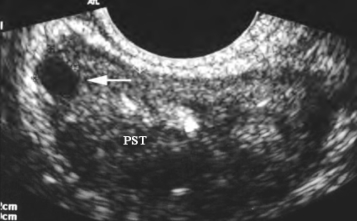

3.早期癌在外腺区通常为低回声结节,少数为等回声或非均质性回声。晚期癌内部回声不均匀,低回声区有散在强回声团块,有声衰减,内腺受压,与外腺分界不清(图31-1)。

图31-1 前列腺癌声像图

经直肠扫查前列腺外腺区局限性低回声(←)